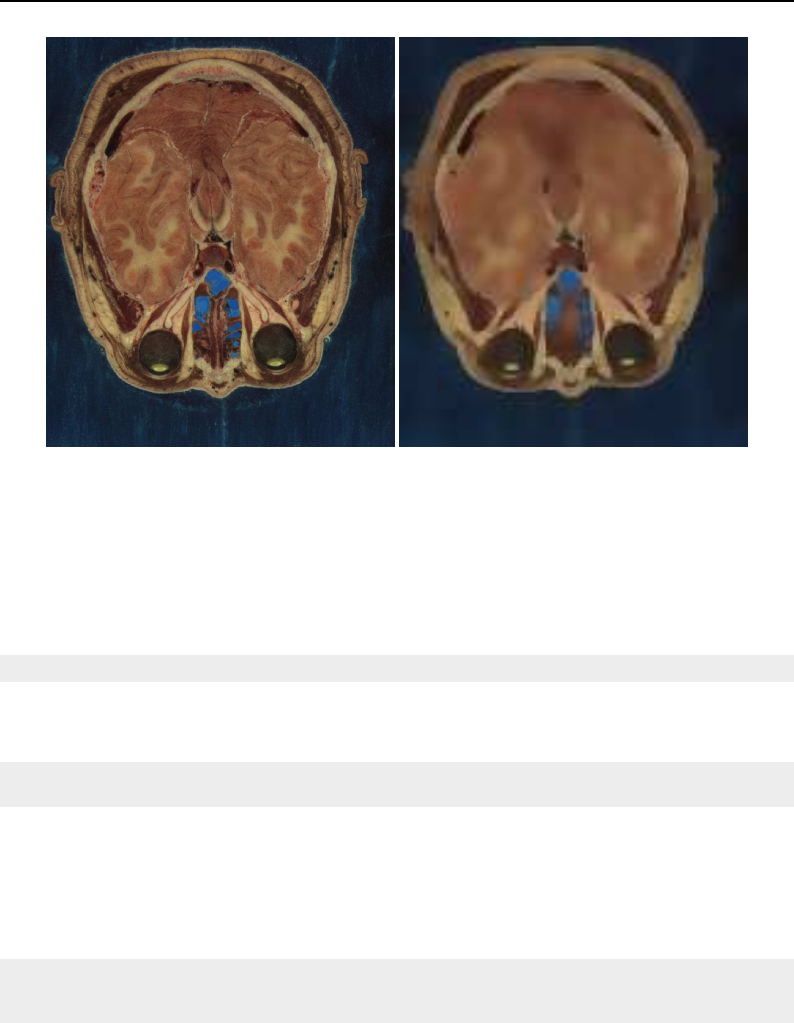

The Insight Toolkit was designed to support the Visible Human Project and its as-

sociated data. This data is available from the National Library of Medicine at

http://www.nlm.nih.gov/research/visible/visible_human.html